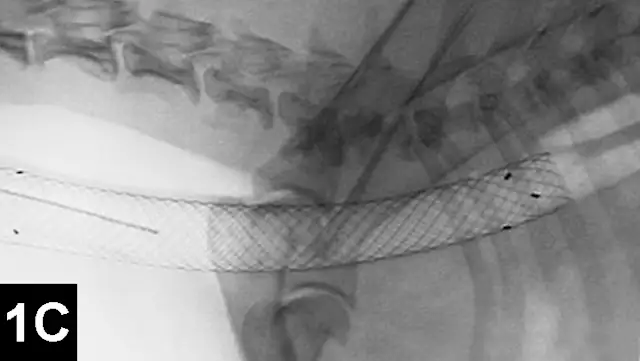

Chemoembolization involves selective delivery of intraarterial chemotherapy with subsequent particle embolization (Figure 4). Instead of administering systemic chemotherapy through a peripheral vein and exposing the patient to high systemic levels of these toxic drugs, local delivery into the arterial supply of the tumor has been shown to increase local drug concentrations, reduce systemic drug levels, reduce associated toxicities, and improve tumor response rates in humans with similar tumors.

Figure 4A: Lateral digital subtraction angiograms of a dog with a nonresectable massive right-sided hepatocellular carcinoma.

The dog’s head is to the left.

Prechemoembolization angiogram demonstrating a massive liver tumor (surrounded by hyphenated line).

The author has performed this procedure in cases of invasive sinus carcinomas and unresectable hepatocellular carcinomas in dogs with encouraging results.13

When chemoembolization is performed in dogs, the author has documented as low as 1/20th the peak concentration of circulating chemotherapeutic agent found systemically as well as systemic chemotherapy exposure, which in turn theoretically reduces the toxic systemic side effects and subsequently results in improved tumor response rates when compared with intravenous administration.